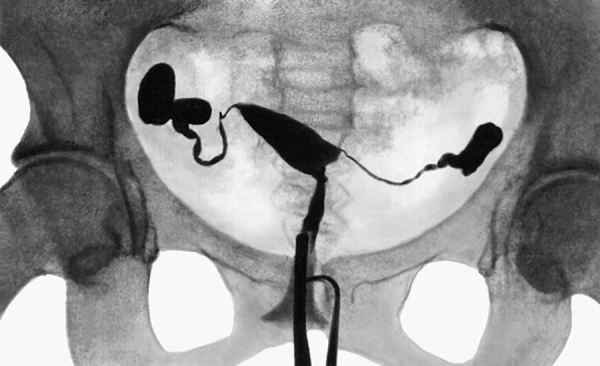

После удачных испытаний в трубке пришло время главного аттракциона. Исследователи напечатали на 3D-принтере реалистичный прозрачный макет женской репродуктивной системы, так называемый фантом. За основу взяли снимки МРТ настоящих органов, чтобы воспроизвести геометрию матки, шейки и двух маточных труб с изгибами и сужениями. Этот гибкий прозрачный орган погрузили в резервуар с физраствором, а внутрь залили тоже солевой раствор. Стартовая позиция спермоботов в области шейки матки. Задача – добраться до конца одной из маточных труб, преодолев всю полость матки и изгиб трубы.

Даже для обычного сперматозоида преодолеть весь этот путь задача не из лёгких, а тут у нас кластер мёртвых клеток с грузом. Вращающийся магнит задали на частоту 1,5 Гц, не слишком быстро, чтобы кластер уверенно катился, не рассыпаясь. Робот-манипулятор программно вёл магнит вдоль рассчитанной траектории: сначала прямо через маточный зев в полость, затем к устью нужной трубы, затем наклонял траекторию вверх по трубе.

Дистанция от старта до финиша примерно 17 см, это реалистичный масштаб человеческой матки и трубы. Время пути около 40 секунд. Средняя скорость, получается, ~4–5 мм/с, но по прямой участки были быстрее (~6 мм/с), а на подъём по трубе медленнее (~3 мм/с).

По ходу движения спермобот иногда раздваивался, часть сперматозоидов могла оторваться и остаться позади, либо кластер делился на 2–3 меньших. Но даже эти мелкие частицы были видны на рентгене (пусть и хуже), и более того, магнитное поле продолжало в целом гнать их вперёд вместе. То есть управление оставалось возможным, просто вместо одного объекта оператор вёл группу мелких. На экране это выглядело как несколько блуждающих огоньков.

Тем не менее основной, самый крупный кластер, как правило, добирался до конца трубы. В некоторых попытках к концу пути на рентгеновском снимке объект терялся, видимо, рассеивался на мелкие фрагменты, контраст падает, и различить их трудно. Даже при невысоком CNR человеческий глаз и мозг угадывают положение микроробота и могут по виду движения корректировать его курс. С опытом, вероятно, можно научиться ловить эту тень более уверенно. Кстати, для улучшения обзора экспериментаторы в какой-то момент повернули систему на 20°, так магнит, вращающийся сверху, не заслонял рентгеновский детектор.

В итоге этот эксперимент стал первым в истории примером одновременной рентгеновской визуализации и магнитного управления био-гибридным микророботом внутри анатомически реалистичной моделиu. На рентген-кадрах видно, как небольшое светлое пятнышко уверенно ползёт из шейки к правой трубе, затем к левой, как по мановению волшебной палочки (а точнее, внешнего магнита).